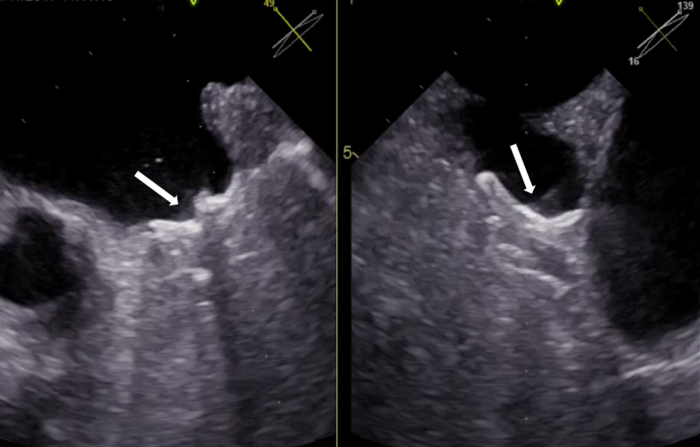

Skopia rentgenowska – zakontrastowane uszko lewego przedsionka

W lewym przedsionku serca znajduje się nieduża nisza, która nazywana jest uszkiem lewego przedsionka. U zdrowego człowieka krew po prostu przez wspominane uszko przepływa. Inaczej sytuacja wygląda u osób cierpiących na migotanie przedsionków, u których krew w uszku zatrzymuje się na dłużej, co sprzyja powstawaniu zakrzepów. Gdy taki zakrzep się odczepi i dopłynie do mózgu, powoduje udar. Podstawową formą zapobiegania tym zdarzeniom jest terapia doustnymi lekami przeciwzakrzepowymi.

– Procedura zamykania uszka lewego przedsionka jest wykonywana u chorych z migotaniem przedsionków, którzy mają przeciwwskazania do stosowania doustnych leków przeciwzakrzepowych i polega na implantacji do uszka specjalnego systemu zamykającego, tzw. okludera. Dzięki wypracowaniu doskonałej współpracy między różnymi specjalistami udało się nam uzyskać wysoką skuteczność zabiegów, z niewielkim odsetkiem powikłań poniżej wartości opublikowanych dotychczas w światowych rejestrach klinicznych – relacjonuje dr Dariusz Ciećwierz z I Katedry i Kliniki Kardiologii GUMed.